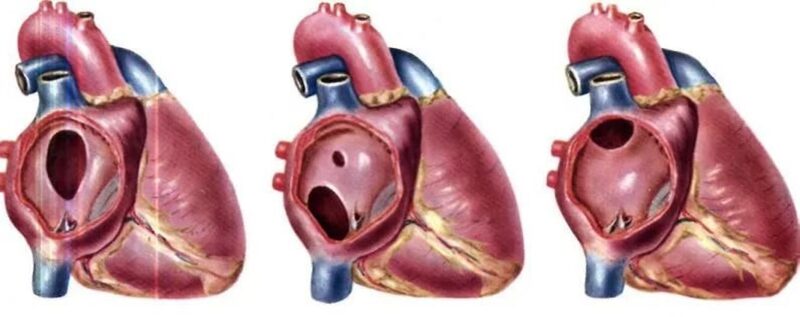

Фотографии и информация о приобретенных пороках сердца